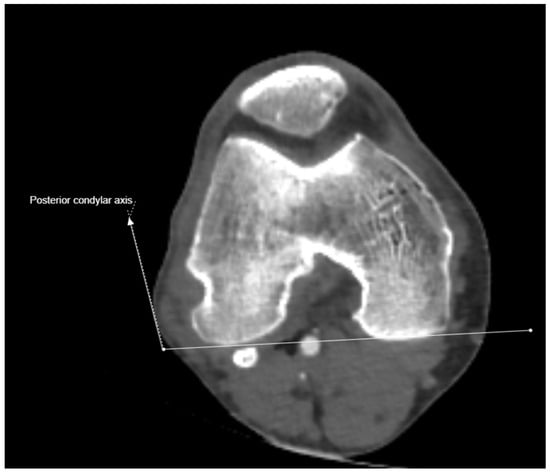

2.3. Imaging and Measurement Methods